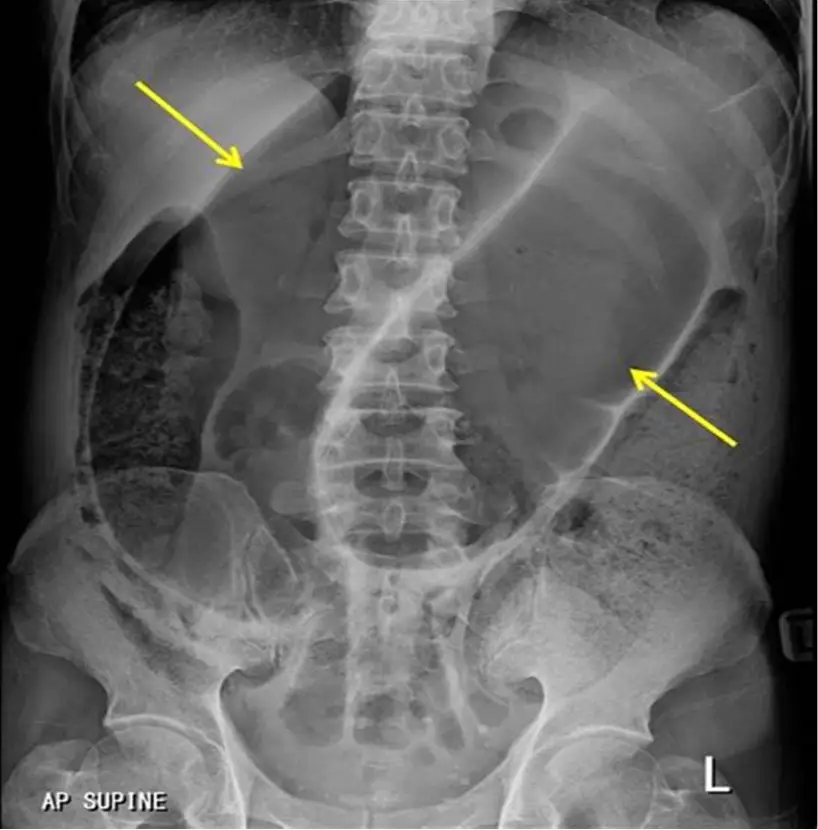

雖然無法直接檢視提供的 X 光影像,但根據題幹描述與正確選項 (C),該腹部 X 光片 (KUB) 必然呈現乙狀結腸扭轉的經典特徵:

1. 咖啡豆徵象 (Coffee Bean Sign):這是乙狀結腸扭轉最具特異性的徵象。影像中會見到一個巨大的充氣腸氣環 (dilated gas-filled loop),形狀像一顆咖啡豆。

2. 倒 U 字型 (Inverted U-shape):擴張的乙狀結腸從骨盆腔 (LLQ) 發起,向上延伸至中腹部甚至橫膈膜下 (RUQ/Epigastrium)。

3. 中央裂隙 (Central Cleft):咖啡豆中間的「裂縫」是由兩層緊貼的乙狀結腸內壁 (medial walls) 所形成,代表扭轉的軸心。

4. 腸壁特徵:由於過度擴張,結腸袋 (haustra) 通常消失,腸壁邊緣平滑。

5. 骨盆腔無氣體:直腸內通常缺乏氣體,因為阻塞點位於乙狀結腸。

3. 影像吻合:題目暗示的 X 光特徵(巨大擴張腸氣環)即為 Coffee Bean Sign。

本題最佳診斷為 (C) 乙狀結腸扭轉 (Sigmoid volvulus)。 患者具備所有經典風險因子:高齡、神經系統退化疾病(帕金森氏症)、長期機構照護或臥床、慢性便秘。帕金森氏症患者因腸道神經叢退化及抗膽鹼藥物使用,導致結腸蠕動變慢與乙狀結腸變長,極易發生扭轉。臨床表現為無痛或輕微腹痛的顯著腹脹,X 光呈現典型的 Coffee Bean Sign。

• 影像 (KUB)Coffee Bean Sign (咖啡豆徵象)、Frimann-Dahl's sign (三條線指向扭轉點)。